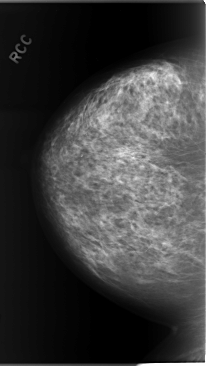

C_0071_1.RIGHT_CC

RIGHT_CC LINES 5848 PIXELS_PER_LINE 3296 BITS_PER_PIXEL 12 RESOLUTION 50 NON_OVERLAY